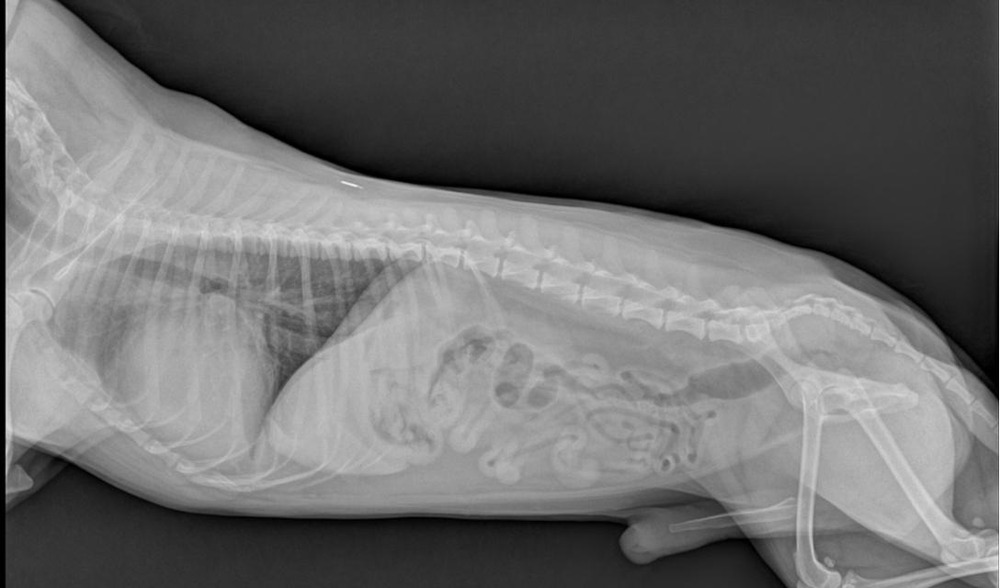

• Echocardiogram (heart ultrasound), this is the most definitive way to assess chamber size and pumping function for DCM.1

• Chest X-ray to check heart size and look for fluid in the lungs when heart failure is suspected.1